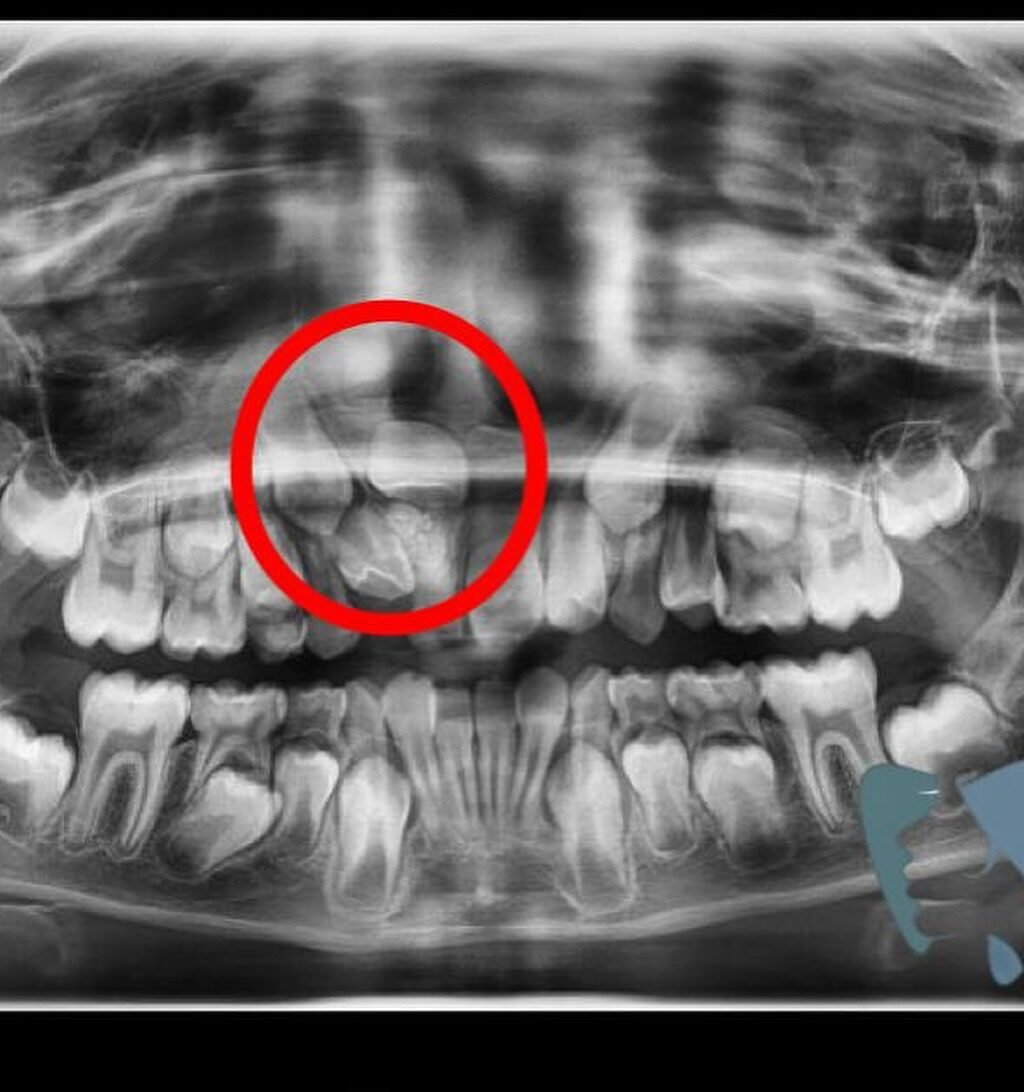

A Patologia Oral e Maxilofacial é a especialidade responsável pelo diagnóstico e tratamento de doenças que afetam a boca, mandíbula e estruturas faciais. Atua na identificação de lesões, cistos e tumores, garantindo diagnóstico preciso e tratamento adequado para preservar a saúde bucal e geral do paciente.